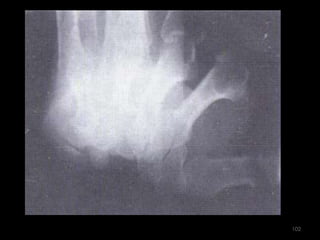

Incidência túnel do carpo súpero-inferior (dorso palmar)97

98

99

Incidência túnel do carpo ínfero-superior – método Gaynor-Hart100

101

102